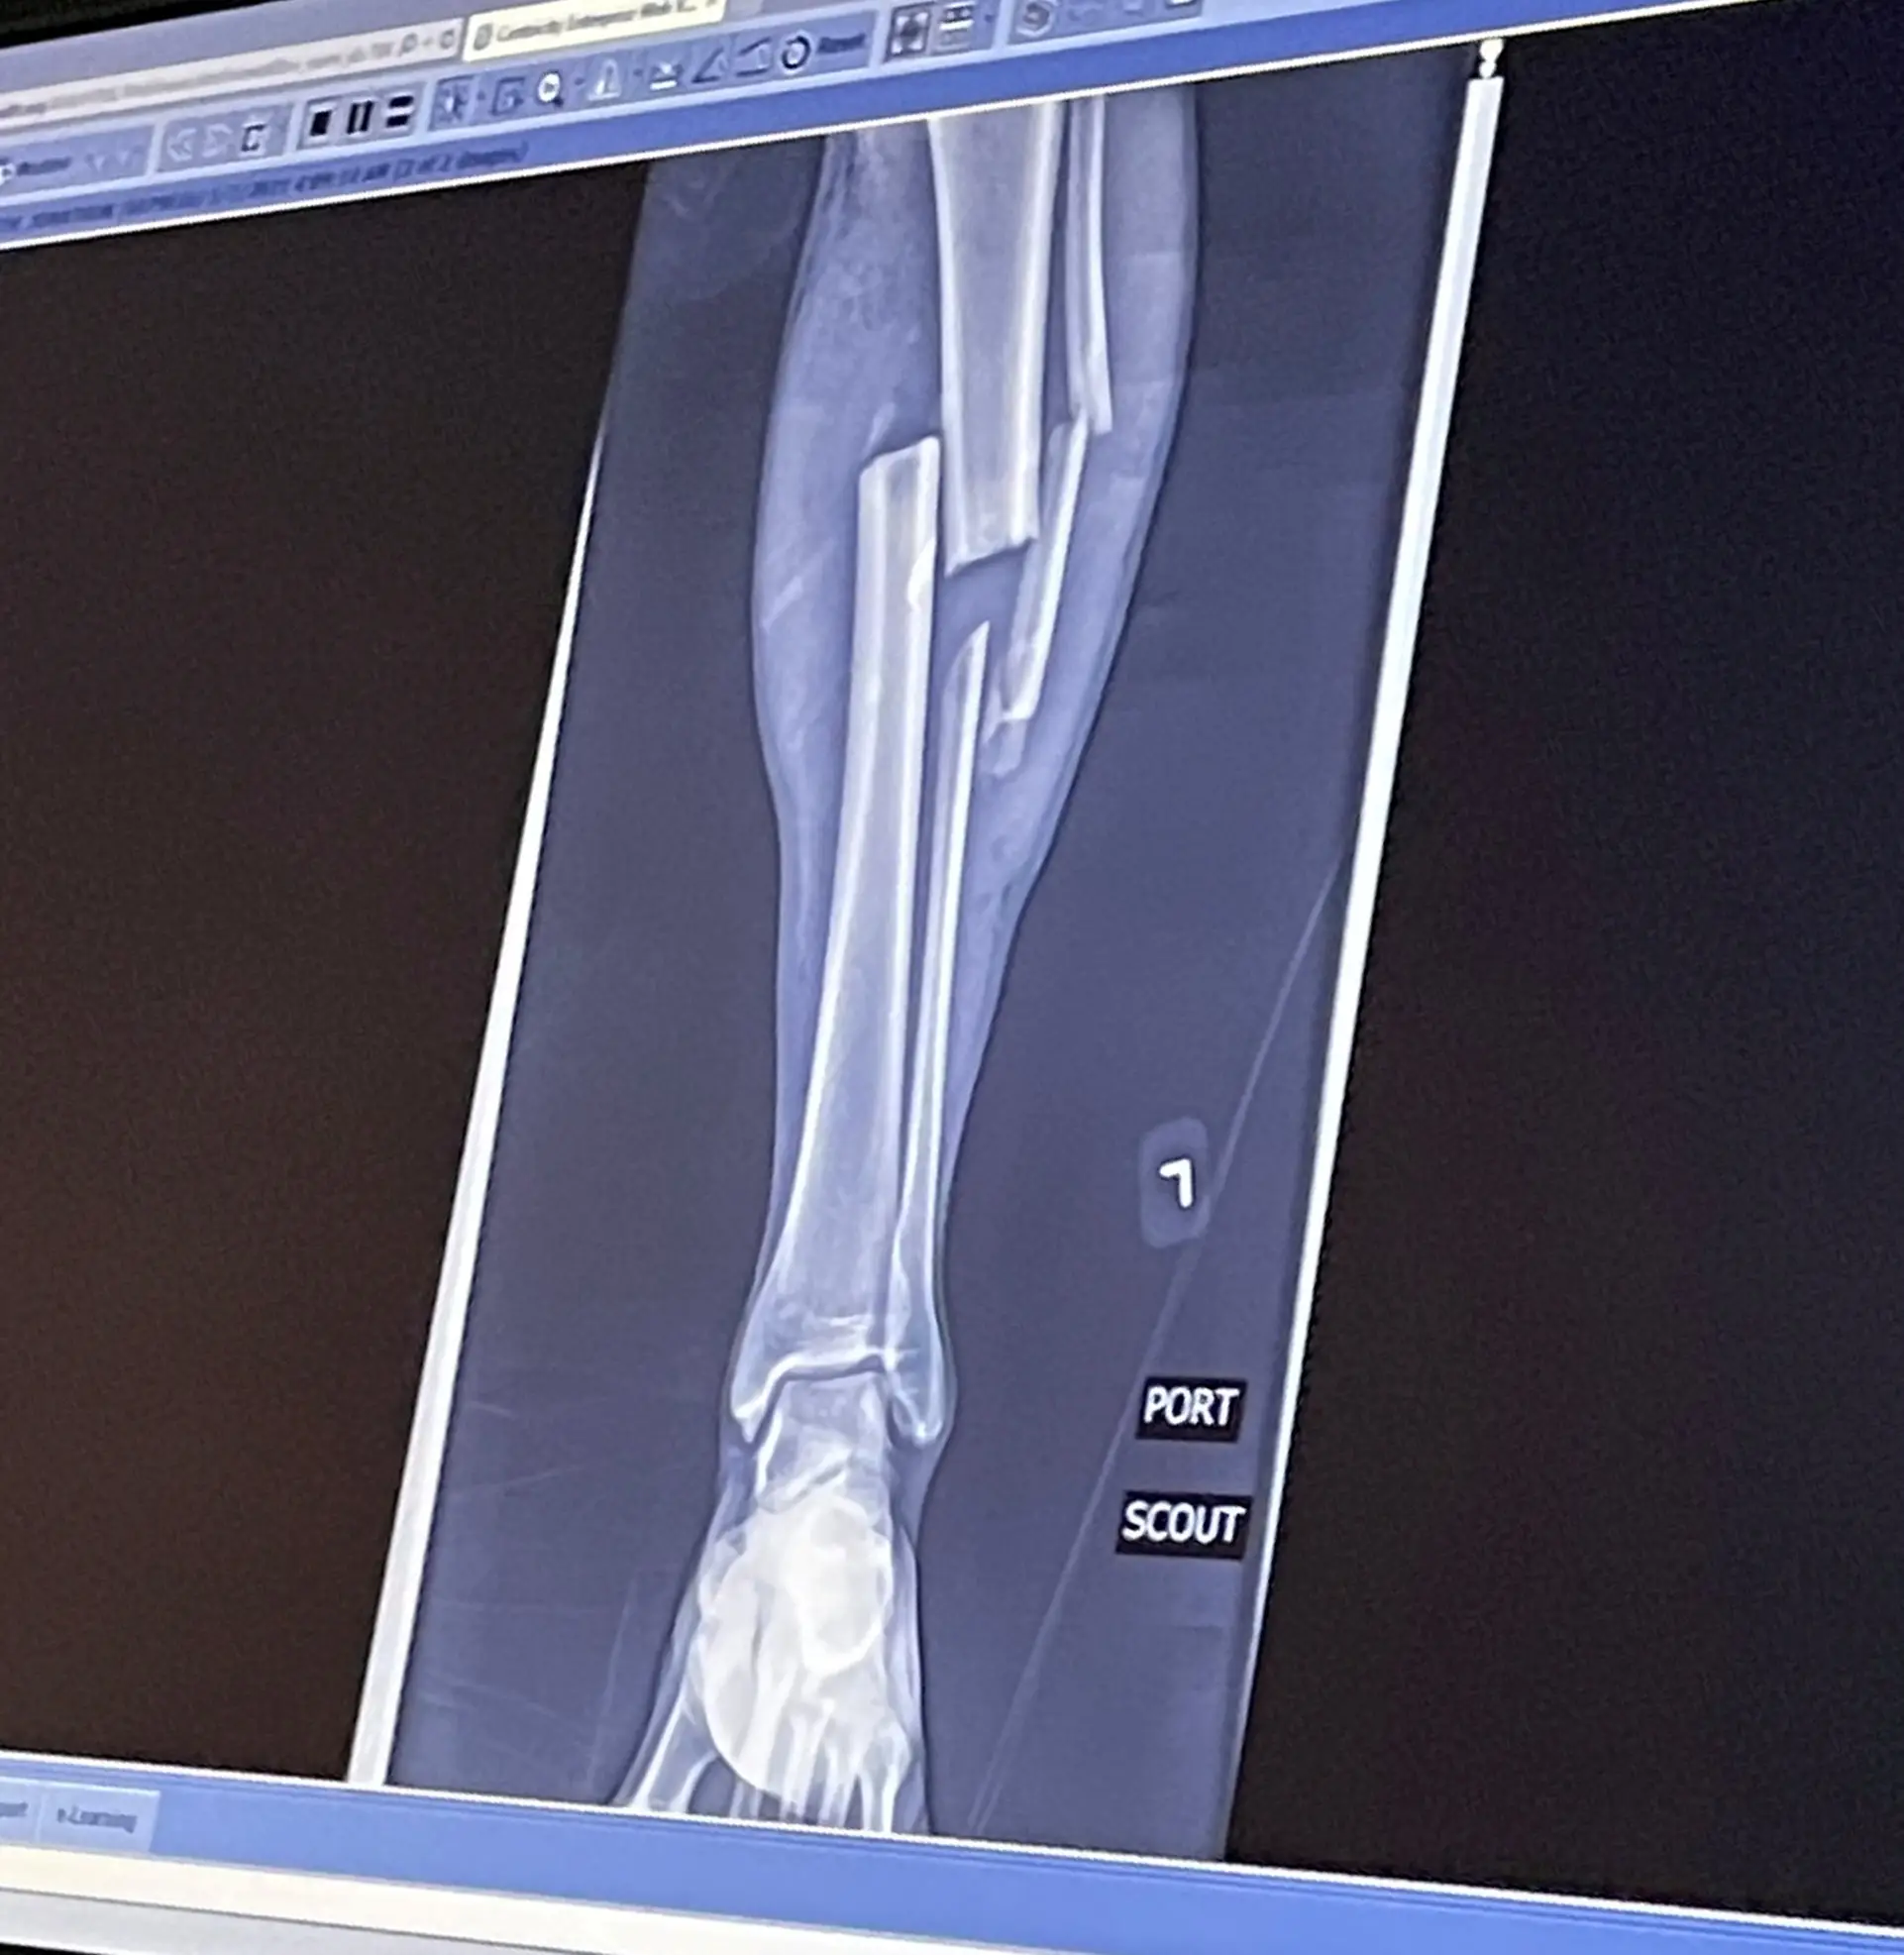

He was rushed to hospital where he was treated for numerous injuries, including two caved in shins, which were so bad the bones had pushed through the skin, and broken bones on both knees.

He also fractured his skull, broken both eye sockets, his nose, his jaw and three ribs.

The most severe injuries were in his legs and his crushed right hand, and his ring, middle and pinkie fingers, as well as part of his palm, were all amputated.

He later had his lower right leg amputated after he was warned he would need up to 12 more surgeries to try and save it.